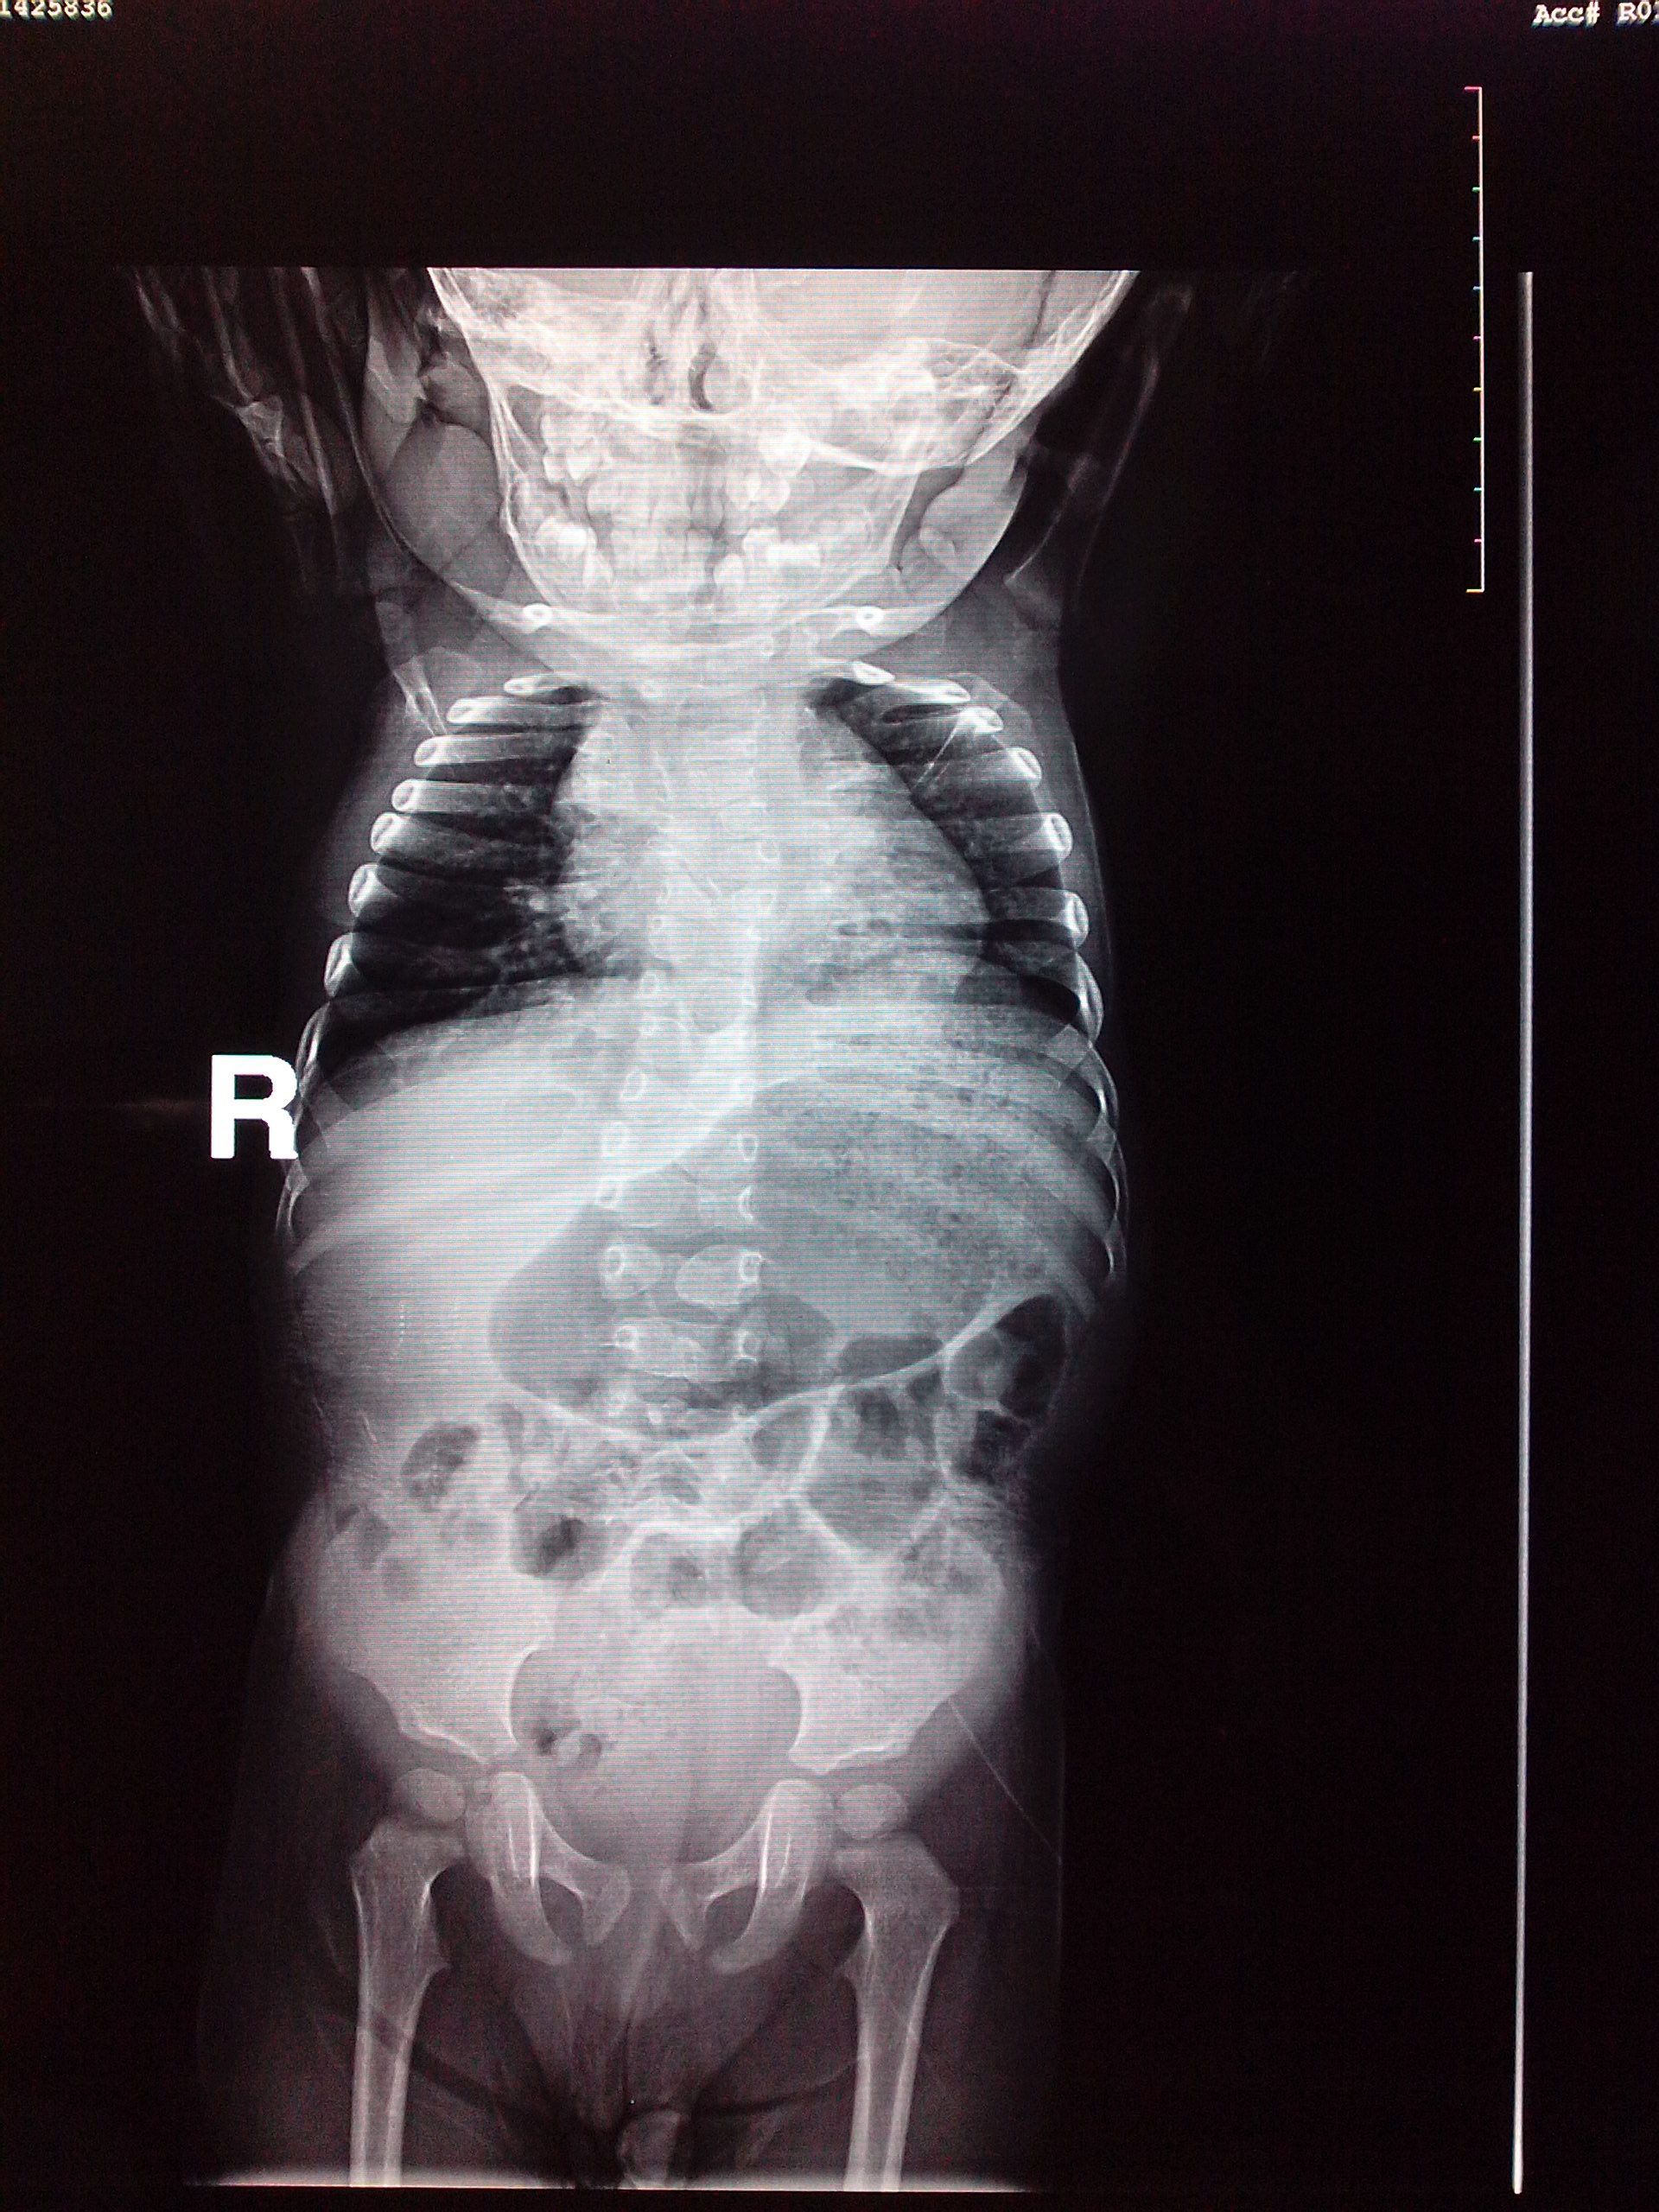

17个月幼儿个小,胸高,颈短,疑先天性疾病,如何治疗?

患者信息:男 1岁 吉林 长春 病情描述(发病时间、主要症状等):17个月幼儿个小(现在身高72cm),胸高(而且右侧明显比左侧高),颈短(且爱向右侧回头,向左侧回头费劲),之前以为是缺钙导致,后来在医院排片检查说是先天性脊柱发育不良,请问该如何治疗?何时治疗合适?(补充一下:孩子现在会走路,能说简单语言,智力正常,活泼,但是不知怎么的,自从吃了补钙药以后不怎么爱吃饭。)想得到怎样的帮助:我上传了影象,麻烦各位大夫帮看一下影象,想知道这样的病能不能治,何时治疗合适?谢谢!曾经治疗情况及是否有过敏、遗传病史:小孩之前在县医院检查说是缺钙,开了些补钙排铅和预防佝偻病的药,一直在补钙可是不怎么吸收,现在在吃迪巧儿童钙片。家人无类似病例。